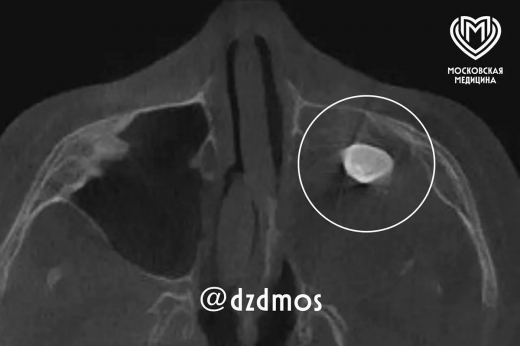

Выросший в носу у 15-летнего москвича зуб нашли врачи Филатовской больницы. Специалистам удалось успешно удалить его, сообщает столичный депздрав в своем канале в Max . Изначально подросток обратился к докторам из-за асимметрии лица и заложенности носа. Уточняется, что зуб у мальчика в гайморовой пазухе уже ранее нашли в частной клинике, однако родители хотели послушать стороннее мнение экспертов. В Филатовской больнице операцию предложили провести по Колдуэллу-Люку, обеспечив доступ через верхнюю десну, чтобы вернуть подростку возможность нормально дышать. Сделав разрез, медики обнаружили новообразование — доброкачественную опухоль, в которой находился зуб. Операция прошла успешно, на данный момент пациента выписали, заложенность носа, мучившая его, исчезла. Также разрешились проблемы с асимметрией. Ранее был назван снижающий риск развития кариеса десерт.